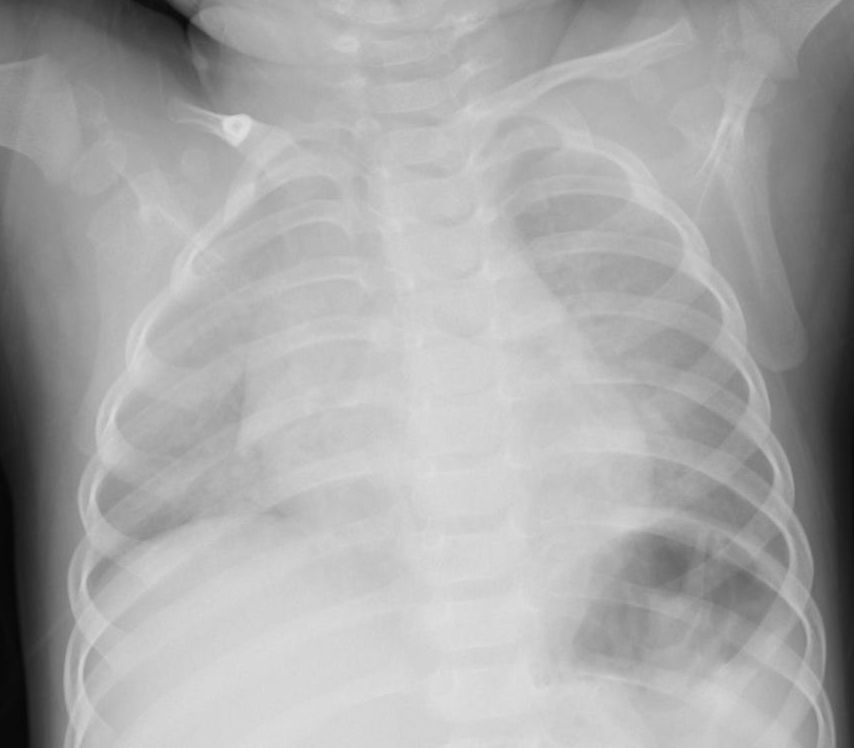

肺野の含気過多があり細気管支炎様のレントゲン像だが、同時に上縦隔右気管支上の部分が反対側の左と比べてやや白く透過性が悪くなっている。このような場合気管支S1もしくはS2の浸潤影初期のことがある。

5日後に確認したレントゲン像を下に提示する。